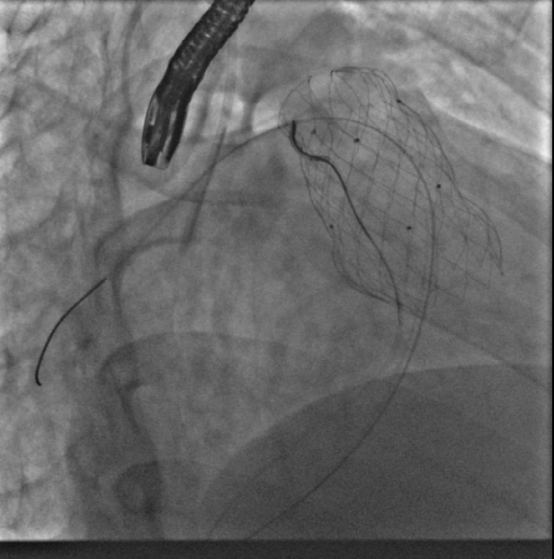

10月12日,葛均波院士、周达新教授团队直播为一名特殊的患者进行TAVR手术,该患者仅有44岁,但因为维持性血透,严重心功能不全,射血分数只有25%,外科医生评估外科手术风险极高,因而转为TAVR手术。

术中由于患者心功能此前已经严重受损,在球囊扩张后由于瓣膜狭窄解除,反流加重出现心脏停跳循环崩溃,体循环血压降至30mmHg以下,周达新主任经验丰富迅速为患者进行胸外按压并同时使用血管活性药物,将患者的血压维持在100mmHg左右,直至其心脏自主收缩恢复。

在瓣膜释放过程中,因为29mm瓣膜太大,患者又是二叶瓣主动脉瓣,导致尽管在瓣膜释放过程中进行快速起搏控制血压,但瓣膜释放过程中数次出现定位困难,一次上弹至升主动脉的过程中,导丝损伤打折,导致瓣膜输送系统与导丝间摩擦力过大,输送系统一时回撤困难,周达新教授用持针器固定导丝,最终成功回撤瓣膜输送系统。但在随后使用6F猪尾巴交替受损的Safari导丝时,因为损伤部位折角过大,猪尾巴管无法通过损伤部位,团队迅速更换6F大腔导管,顺利通过受损导丝到达左心室,使用交换导丝,再上6F猪尾巴管,重新导丝建立轨道。

考虑到瓣膜在释放过程中定位困难,周达新教授在瓣膜释放开始出现下滑后,将瓣膜回收一点后上提紧贴自身瓣膜,再迅速释放,最终使得瓣膜完全固定。因为患者是type0式二叶瓣,瓣膜释放后,支架展开不良,准备予以球囊后扩张,但是食道超声发现左冠窦内可疑有扩碎的瓣叶在飘动。考虑患者的窦部宽大,冠脉堵塞风险较小后还是予以球囊扩张,同时造影看到左右冠血流可。球囊扩张后瓣膜之间展开良好。

虽然手术过程中经历一波三折,但周达新教授沉着应对,团队最终顺利的完成了手术,面对直播镜头,周达新主任及其团队展示了高水平的手术技巧,更展示了强大的心理素质和丰富的手术经验。